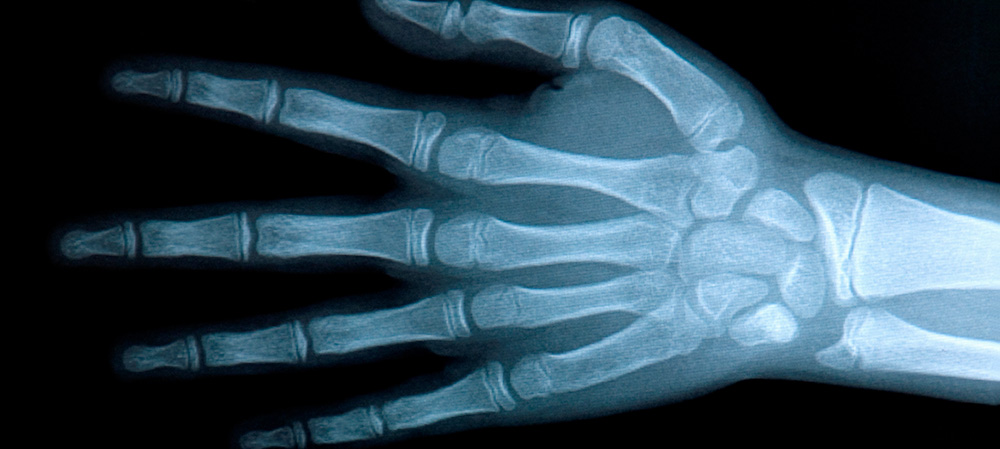

Provádíme veškerá RTG vyšetření kostí, páteře, lebky, plic a břicha včetně speciálních projekcí. RTG snímky jsou pořizovány v digitální formě na systému FUJI.

Veškerá RTG vyšetření provádíme bez objednání. Snímky pořízené od 8.00 do 12.00 popisujeme ihned, odpolední pak druhý den.